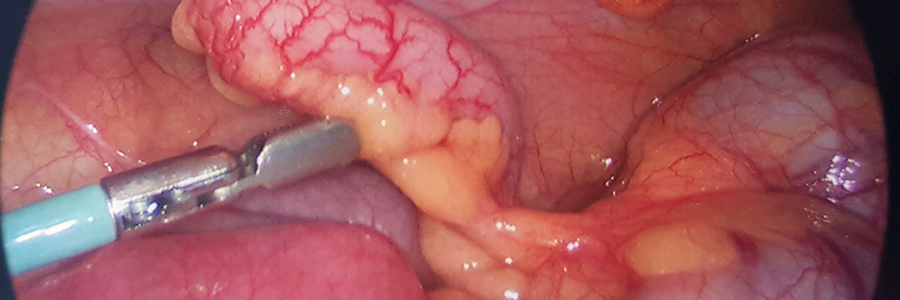

• Laparoscopic surgeries

(a) Gall Bladder Surgery (Open/ Laparoscopic Surgery)

Gall Bladder Surgery

The gallbladder may be a small organ located on the underside of the liver. Its primary purpose is bile storage. Gallbladder removal may be a surgery to get rid of the gallbladder via one, large open incision within the abdomen. It’s also called an open cholecystectomy. The procedure is performed to supply permanent relief to an individual with gallstones and other problems related to the gallbladder.